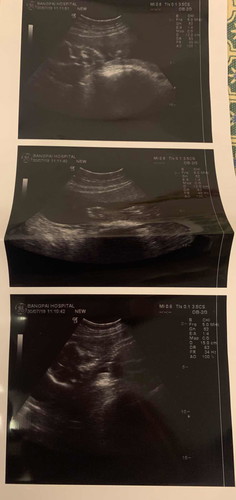

อยากคอนเฟริมผลอัลตร้าซาวน์หน่อยคะ พอดีตอนซาวหมอโดนเร่งให้ไปห้องคลอดต่อ เราได้เห็นจอแปปเดียวเองคะ ไม่มีเวลาได้คุยกับหมอเลย แต่หมอบอกว่า ผู้ชาย 80% กว่าจะได้เจอหมอซาวอีกทีก็ตอนแปดเดือนเลย แม่ๆคนไหนพอดูออกไหมคะ ว่าเพศอยู่ตรงไหน แล้วเป็นผู้ชายจริงไหมคะ